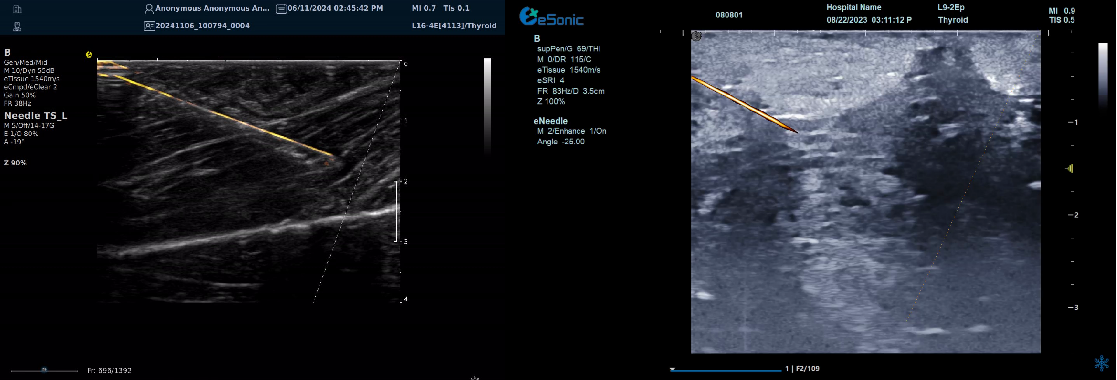

智能介入解决方案-----  穿刺针增强技术

?指示针尖位置、提高针道显示

?穿刺针智能彩色map,有效区分针尖与神经肌腱组织,

尤其在热消融时空化组织不影响针尖显示

?无磁导航:精准制导、自动追踪

?智能识别、路径预判

--引导延长线随针尖转动实时偏转